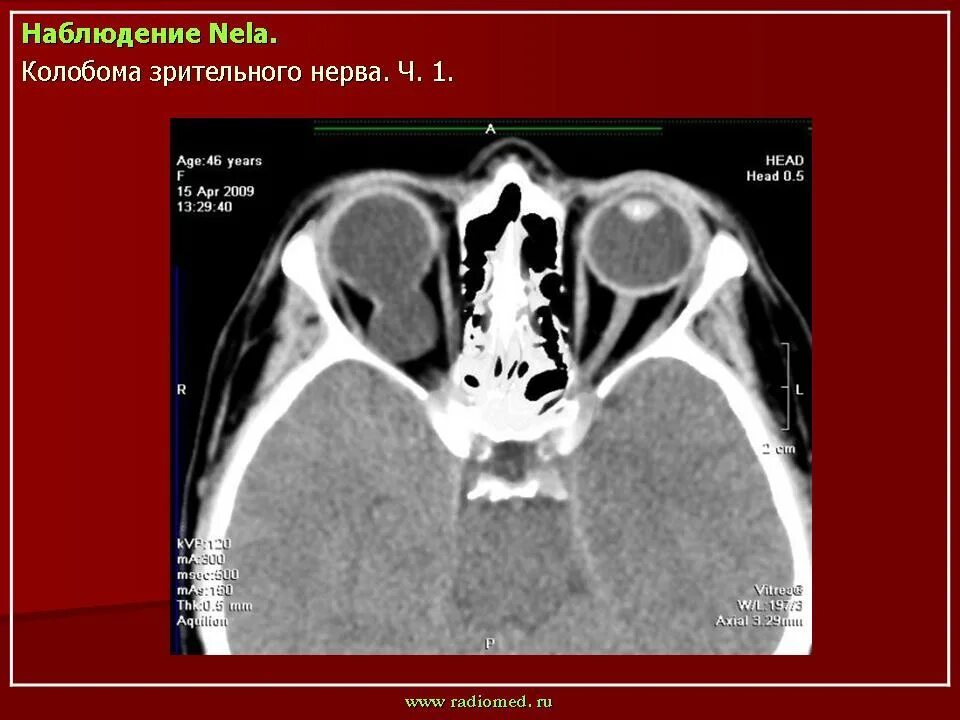

Данные кт